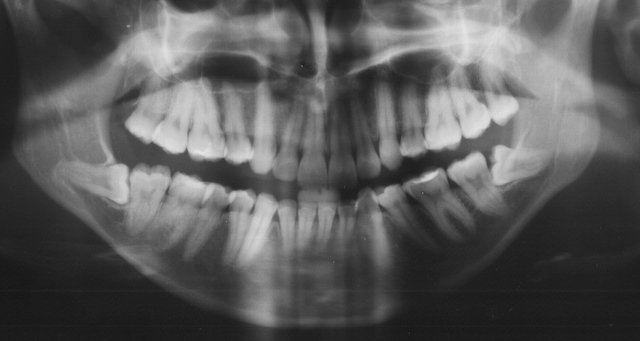

Algumas pessoas não possuem mesmo o dente do siso (o germe dental); outro motivo pelo qual o siso não “nasce” é a falta de espaço na arcada dental, ou ainda, pela sua posição horizontal – dente “deitado”.

A erupção parcial ocorre geralmente por falta de espaço na arcada ou pela posição horizontal do dente (só aparece a “ponta” do dente na boca). Esse quadro pode provocar gengivites e abscessos na região, irritação local, dor e inchaço. No dente vizinho ele também pode provocar doença periodontal e lesão de cárie. Todos estes problemas se devem à dificuldade que o paciente tem para higienizar este dente e de uma gengiva de baixa qualidade ao redor dele!